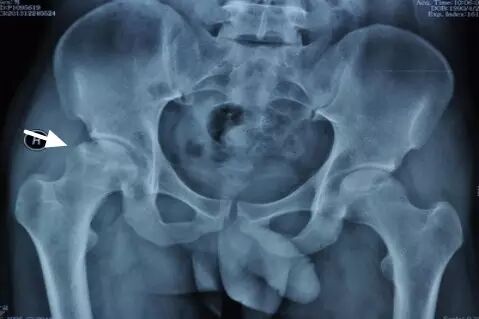

IV期X线片显示股骨头变扁

IV期、V期和VI期的患者,由于股骨头坏死已经导致股骨头塌陷变形,所以只能行全髋关节置换术。并且尽量在VI期以前完成手术,因为一旦髋臼出现严重磨损、骨缺损,会显著降低人工关节假体的稳定性和使用寿命。人工关节置换手术以后第二天就可以下地行走,可以下蹲和跑步,不再需要服用药物,生活同常人无异。